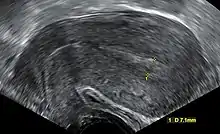

Transvaginal ultrasonography after an episode of heavy bleeding in an intrauterine pregnancy that had been confirmed by previous ultrasonography. There is some widening between the uterine walls, but no sign of any gestational sac, thus, in this case, being diagnostic of a complete miscarriage.

A complete miscarriage is when all products of conception have been expelled; these may include the trophoblast, chorionic villi, gestational sac, yolk sac, and fetal pole (embryo); or later in pregnancy the fetus, umbilical cord, placenta, amniotic fluid, and amniotic membrane. The presence of a pregnancy test that is still positive, as well as an empty uterus upon transvaginal ultrasonography, does, however, fulfil the definition of pregnancy of unknown location. Therefore, there may be a need for follow-up pregnancy tests to ensure that there is no remaining pregnancy, including ectopic pregnancy.